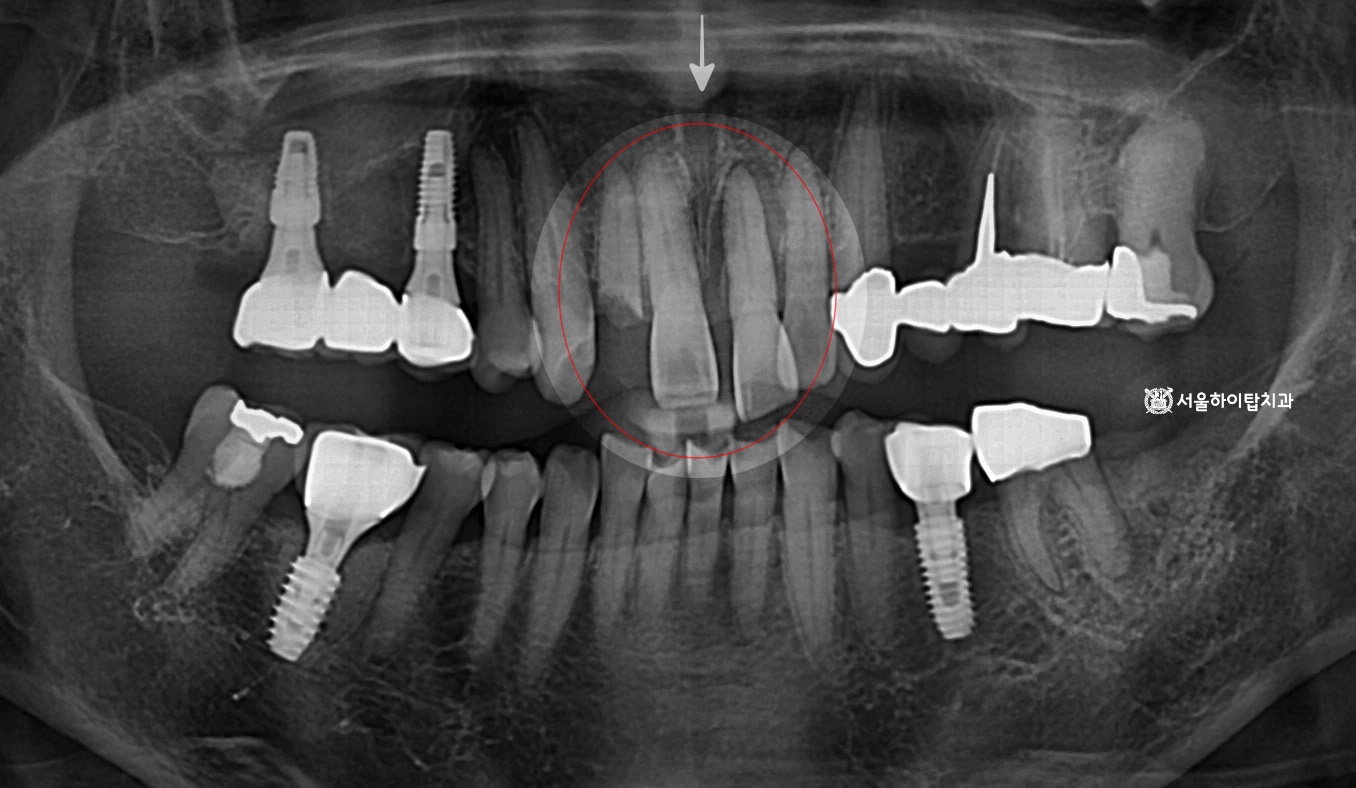

십정동 치과 상실된 치아가 불러오는 연쇄적 문제? 치조골 흡수와 기울어진 어금니, 뼈이식 동반 임플란트 과정 동암역 치과 : 균형 잡힌 저작이 중요한 이유, 전반적으로 손상된 치아 및 잇몸 임플란트를 통해 저작 기능 개선 간석역 치과 치주염으로 인한 치조골 흡수, 치아 파절 및 마모까지 임플란트 가상 시뮬레이션을 통한 안전한 수술 과정 1 2 Next Archives 2026년 4월 2026년 3월 2026년 2월 2026년 1월 2025년 12월 2025년 11월 Categories 미분류 신경치료 심미 치료 임플란트